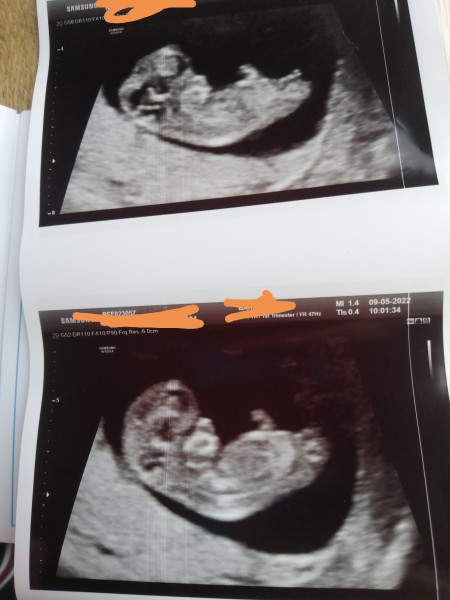

Kathno4 · 07/05/2022 04:19

@Bramblecrumble21 lovely scan! Awesome when they’re active. I kinda felt I got some of babies personality from just looking at the scan already.

Bramblecrumble21 · 07/05/2022 10:52

@Kathno4 yes, last time the somographer let my DH have a go with the probe at the end and my DD rolled over when I was laughing. Now she'll roll over and pull the covers up in the morning and say she's still sleeping. Haha. Sorry to hear about your symptoms. I feel bad moaning about my headache which are irritating and distracting but not debilitating. My first pregnancy felt like forever. But for me April has gone quite quick. I don't agree that the 6 months wait will fly by, maybe for my DH.